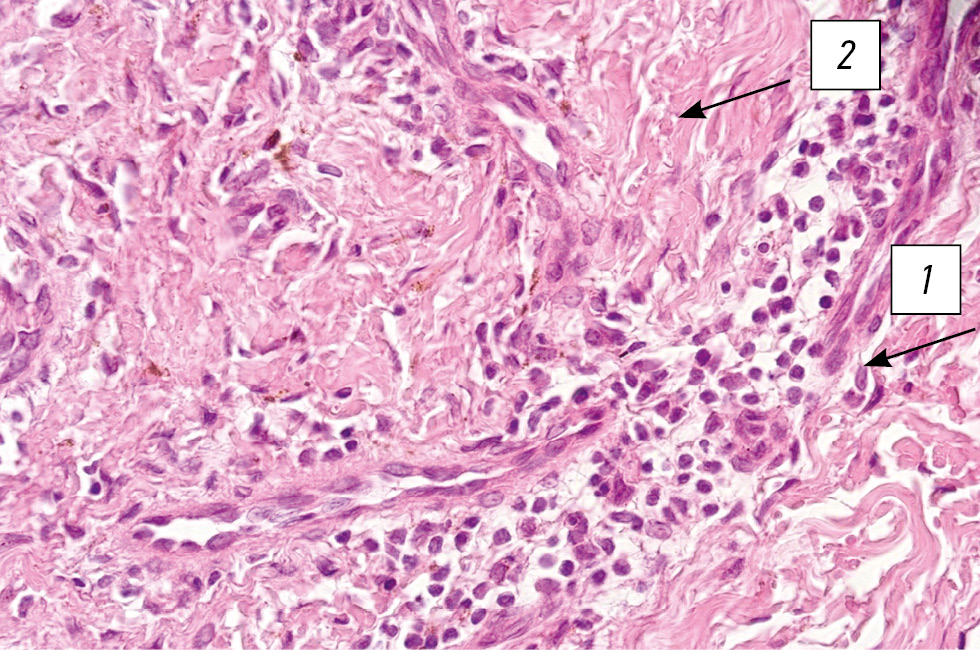

Рис. 7. Гистологическое исследование: в сосочковом и подсосочковом слое дермы ― полосовидный умеренный инфильтрат из лимфоидных элементов, гистиоцитов (1). В дерме незначительный отёк, расширение сосудов (2). Окраска гематоксилином-эозином, ×400.

Fig. 7. Histological examination: in the papillary and sub-papillary layers of the dermis, there is a strip-like moderate infiltrate of lymphoid elements, histiocytes (1). In the dermis, there is slight edema, vasodilation (2). Staining with hematoxylin-eosin, ×400.